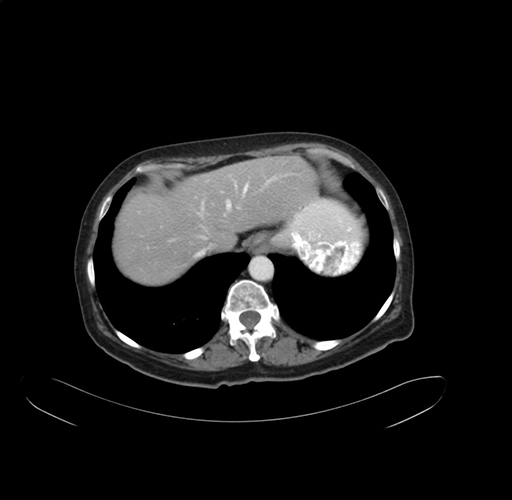

Pre-Chemo: Axial Venous